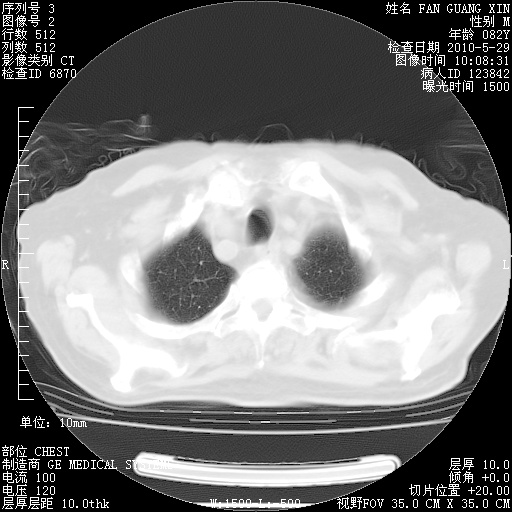

再治疗10天后的肺部CT

阅读此次胸部CT,肺间质渗出性改变较入院时有吸收。目前从体温、白细胞、中性分叶明显增高,肯定存在细菌感染(发生医院感染哦,若无消化道及泌尿系统等感染的依据,肺部感染可能大)。若你院头孢哌酮舒巴坦钠耐药率较高,同意你的方案,若48小时体温仍高,可考虑使用碳青霉稀类抗菌药物,同时可予超声雾化、注意滴数时加大液体量。白蛋白33.30g/L较低哦,需加强营养等支持治疗。

从白细胞总数和中性比例看好像合并感染。肺部纹理好像比上次多,支气管炎?其他感染?